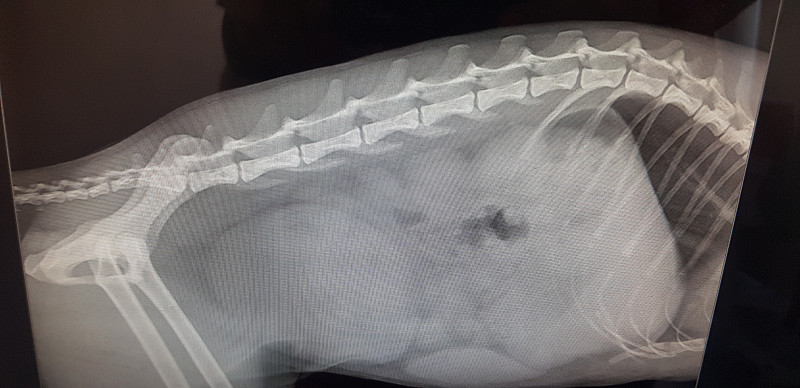

Выполнен рентген брюшной полости. (Снимки прикладываю как фото)